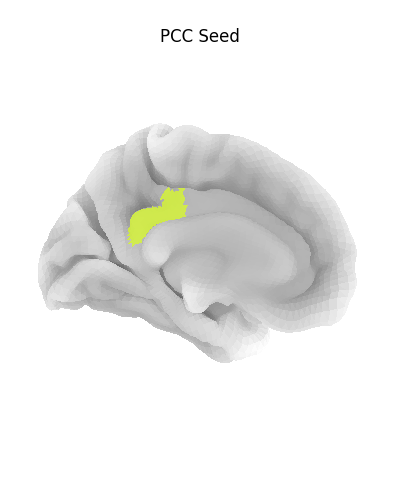

7.6. Surface plotting¶

Plotting functions required to plot surface data or statistical maps on a brain surface.

Added in version 0.3.

|